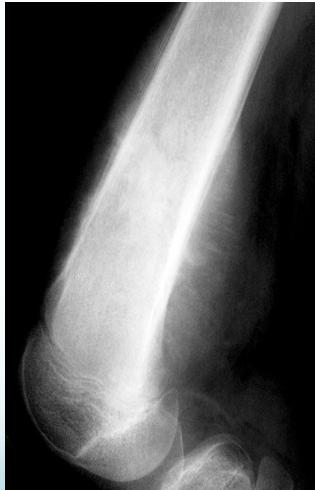

Radiological Features

- X-ray:

- Diaphyseal

- Bone destruction

- New bone formation:

- Along the bone

- “Onion-peel” layers

- ? “Sun-ray”

- ? Codman’s triangle

- Secondaries – in skeleton

Source: Apley’s System of Orthop. And Fractures